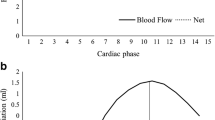

Arterial spin labelling (ASL) is a MRI method for imaging the brain perfusion, and since magnetically labelled blood rather than contrast agent is used as a tracer, ASL is completely non-invasive. Post-labelling delay (PLD) time reflects the time allowed for the labelled blood to travel from the labelling region to the imaging region, and the recommended PLD for a healthy adult is around 2 s [7]. For patients with steno-occlusive disease, the blood usually takes longer time to arrive at the designated imaging region, i.e., a prolonged arterial transit time (ATT) compared to healthy subjects. When the ATT is longer than PLD, blood will still be contained in the vessels at the time of imaging which would lead to bright vascular signal and hypoperfusion in some brain regions. Based on this phenomenon, the signal heterogeneity in ASL images, expressed as spatial coefficient of variation (CoV), was shown to be strongly correlated with ATT [8]. Moreover, ATT has been reported as a predictor of CVR either in ASL or dynamic susceptibility contrast (DSC) MRI [9, 10].

The CoV of CBF as the standard deviation (σ) of ASL CBF divided by the mean CBF (μ) was also derived. CoV was calculated within the whole brain (gray matter and white matter) from non-selective standard ASL.